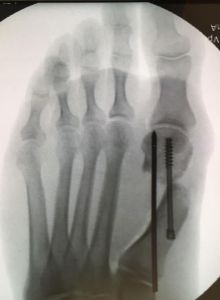

From: Alireza Khosroabadi, DPM

I am glad there has been some discussion here regarding this MIS bunion procedure. I refer to this procedure as a transverse percutenous neck osteotomy. I have been performing this procedure for the past 4 years. I have performed close to 400 of these and have had my share of complications. As with any surgical procedure, once you perform enough of them, you start encountering complications. I have and still continue modifying this procedure to make it better and at the same time, pushing the limits of it. This procedure is extremely powerful. I have performed this procedure on patients of all ages...my youngest patient being 17 and the oldest 82. I have had some minor complications such as pin track infections, and some major such as delayed unions.

Post-op x-ray - MIS transverse percutenous neck osteotomy |

What you see in this x-ray is how I perform this procedure now. This is probably my 6th or 7th modification of...

Editor's note: Dr. Khosroabadi's extended-length letter can be read here.